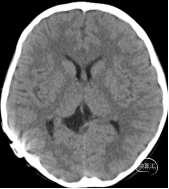

第4日复查颅脑CT平扫提示(如下图)提示:右侧脑室囊肿引流术后,脑水肿较前改善,侧脑室较前略增大。根据患儿目前情况及影像学特点,进一步证实“裂隙脑室综合征”诊断。